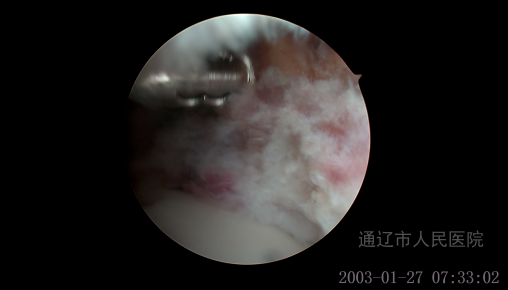

术中缝合修整撕裂的盂唇,打磨凸轮增生: